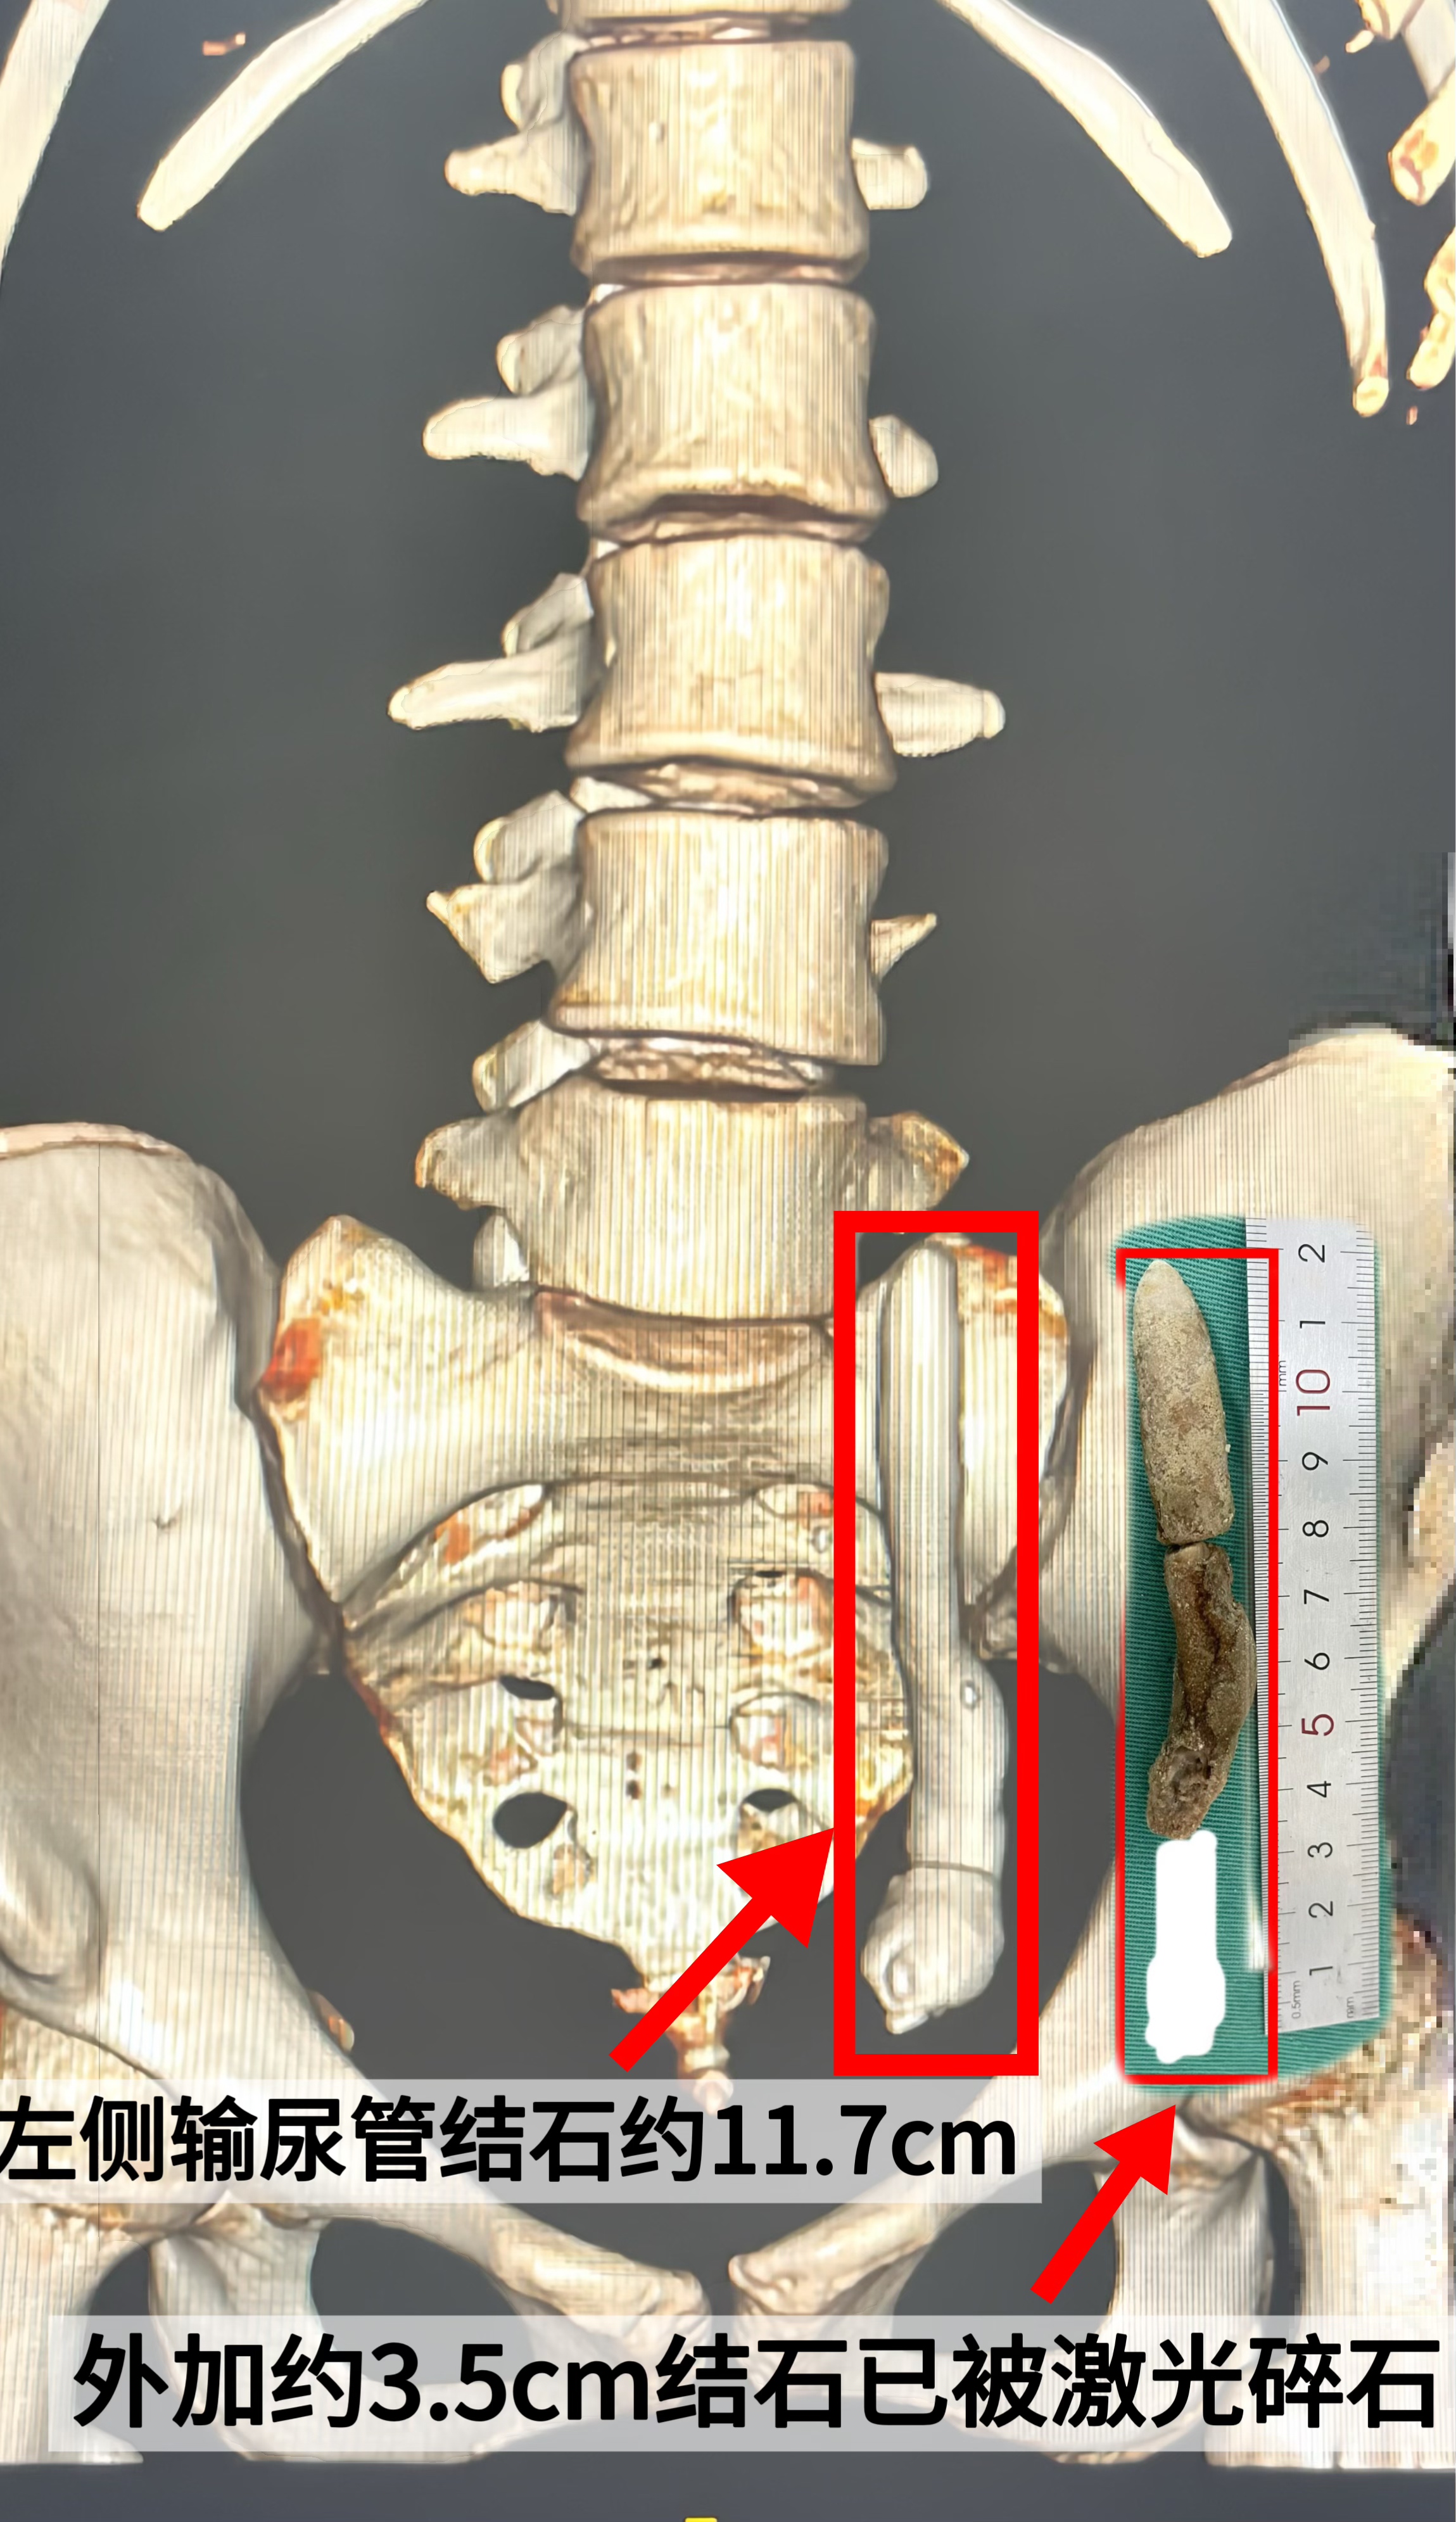

近日,16岁的林女士突然感觉左侧腰部持续疼痛,遂与家属一同前往永泰圣德医院就诊。经医院门诊评估,她被诊断为“输尿管结石”。检查显示,林女士的左侧输尿管下段结石117mm×14mm、CT值约800Hu。

考虑到以上状况,医疗团队创新提出“双镜联合”技术碎石手术方案,即结合经腹腔镜辅助输尿管切开取石与经尿道输尿管镜钬激光碎石两种先进技术一次性清除结石,不仅显著提升了碎石与清石效率,有效缩短了手术时长,更在减少手术创伤方面展现出卓越优势,为患者的疾病治疗及整体预后带来了积极影响。